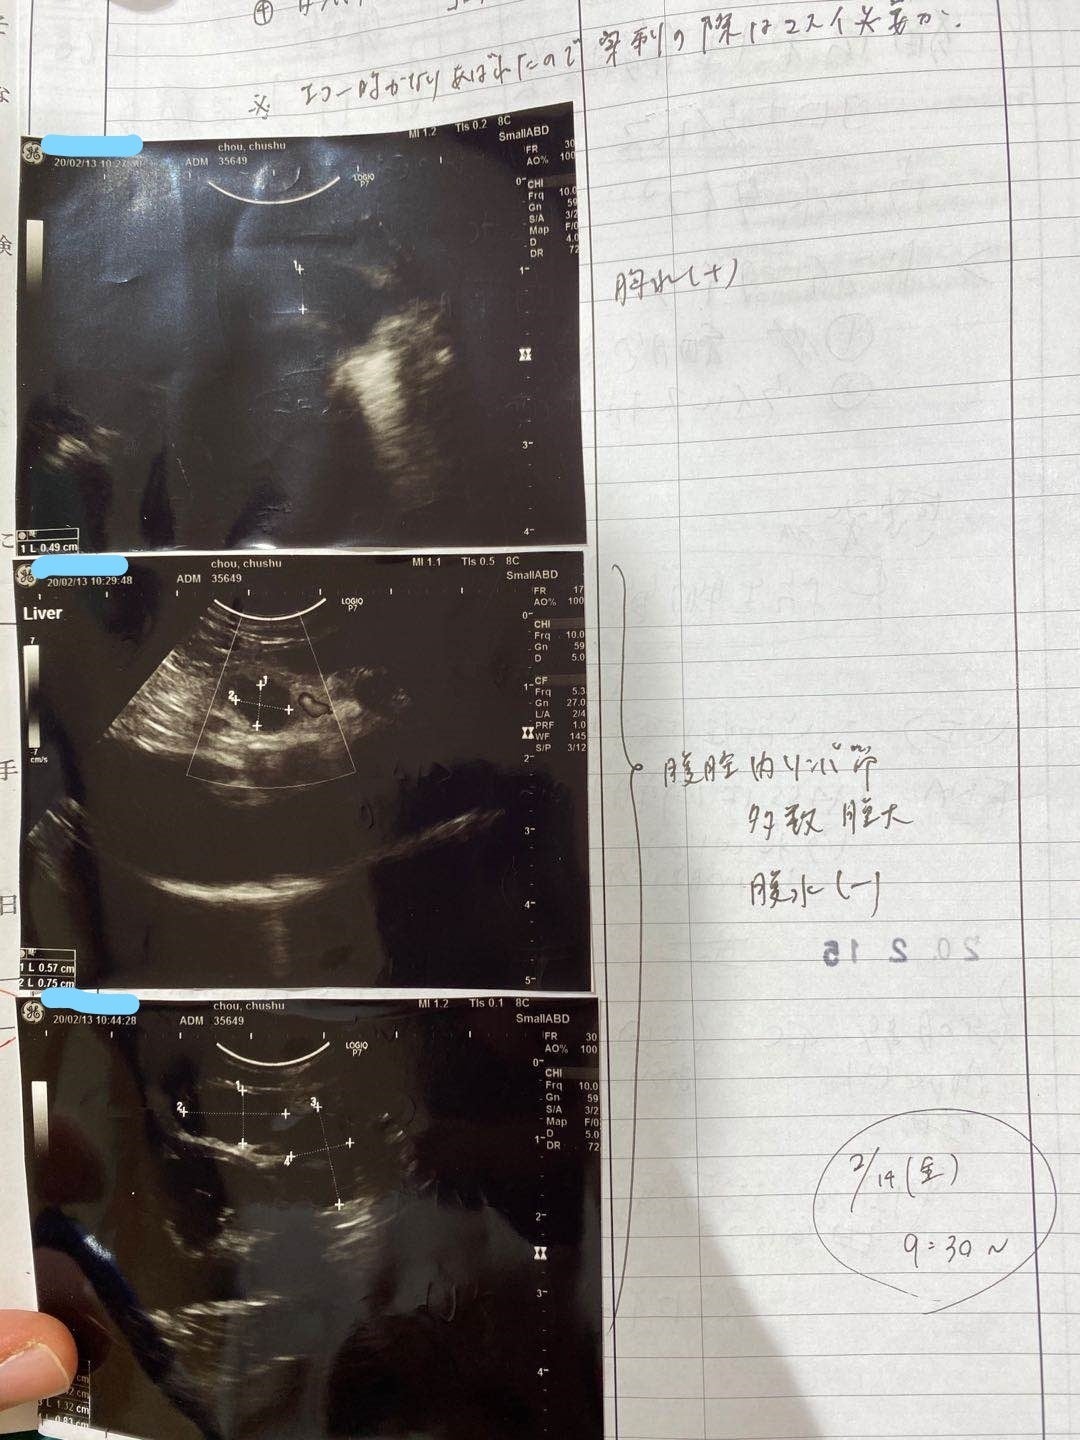

2/13去勢手術するため、身体検査をするとき、肺の中に薄い水影があって、念のため詳しい検査を行いました。

症状が軽い、判断が難しく、少し観察の時間が必要けど、最悪の場合はFIPを罹っているの可能性があると言われて、でも別の病気の可能性もあると言われました。3/9でレントゲン検査すると、水影が少し薄くになって、4月の検査も同じになって、FIPの可能性ではないかもと思います。けど、5月の検査はあまり変わらないになって、22日で急に発症になりました。前を振り返って見て、ずっと自分を責め続いている。

5/25家の近くの協力病院に行って、痛く辛い検査をして、中期混合型と診断されました。

腹水がたまっています

肉芽腫が見つかります